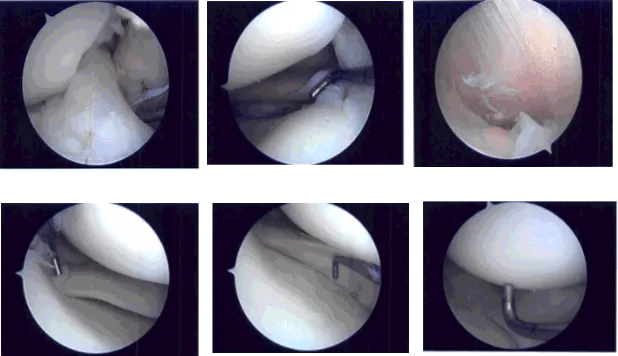

Se construyó un portal de entrada lateral y se accedió al artroscopio. El examen de la articulación patelofemoral no mostró daños. La canaleta medial mostraba escombros. El endoscopio se trasladó al compartimento tibiofemoral medial, donde se pudo ver una pequeña rotura en el cuerno posterior del menisco medial.

Se realizó un portal de acceso médico con el uso de una aguja espinal. Se entró en la sonda y se confirmaron las lágrimas. El desgarro se eliminó usando mordida ascendente y afeitadora. El resto del menisco estaba estable. El endoscopio se trasladó a la zona intercondilar donde el LCA estaba intacto.

El endoscopio se trasladó al compartimento tibiofemoral lateral. Había una pequeña rotura en el cuerno posterior del menisco lateral. El desgarro se eliminó con el uso de una afeitadora. El resto del menisco estaba intacto. No hubo movimiento excesivo del menisco.

El cartílago del cóndilo femoral medial y lateral permanecía intacto. El endoscopio de la rodilla se introdujo en la articulación patelofemoral. El examen de la tróclea y la superficie posterior de la rótula circular se encontró intacto. No se encontraron cambios artríticos. La rodilla fue completamente irrigada y drenada.

Foto intraoperatoria